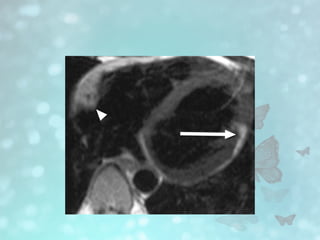

• #15 Black blood breath-hold T1-weighted MR image shows diffuse fatty infiltration of right ventricle. Note increased signal intensity from fat in free wall of right ventricle (arrows), compared with intermediate signal intensity from septum and left ventricular wall (arrowheads)